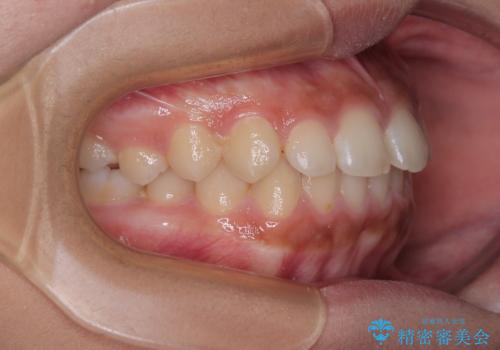

気になるすきっ歯を短期間で改善 インビザライン矯正

- 前歯の隙間を気にして来院された患者様です。

口元の突出感があり、小臼歯4本を抜歯して口元を引っ込める矯正治療も提案しましたが、本人は口元の突出感は気になっていないとのことで、インビザラインにて隙間やデコボコを改善することとしました。

軽度の歯列不正であったため、廉価版のインビザライン・モデレートパッケージにて治療を終えることができました。